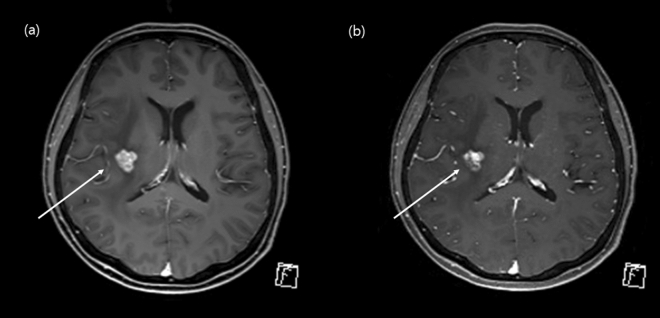

We demonstrated that the contrast-enhanced CS-VIBE may be a feasible and reliable accelerated MR method for the detection of enhancing intracranial lesions (Figs. 5 and 6). Both MPRAGE and VIBE are known to provide T1-weighted images and use spoiled GRE sequences with ultrashort TRs8. MPRAGE requires a prolonged scan time due to the extended magnetization preparation and recovery time before rapid GRE acquisition. On the other hand, VIBE utilizes a fast low-angle shot approach to produce T1-weighted image contrast in steady state imaging. In addition, the VIBE is superior in contrast-enhancement as the short TR of VIBE could increase the SNR and CNR of enhancing lesions8,9. Previous studies found that contrast-enhanced VIBE sequence was an effective, alternative approach to MPRAGE imaging for 3D T1-weighted imaging of the brain which demonstrated superior lesion detection and lesion conspicuity8,9. In this study, we applied CS to further accelerate brain imaging. CS has been used in clinical settings to combine incoherent k-space sampling during acquisition with a dedicated iterative reconstruction algorithm22. Although several studies have shown that the CS technique is useful for reducing the scan time when evaluating the vessel walls or neurovascular compression syndrome18,23,24, CS-VIBE has not been used in various sequences other than the dynamic imaging of the liver or breast with a high spatio-temporal resolution10,11,25. Although we previously found that accelerated CS-VIBE MRI could be a reliable method for the diagnosis of facial neuritis with half the scan time of conventional MPRAGE, the application of CS-VIBE to the CNS remains limited15.

Figure 6.

Comparison of an enhancing intracranial lesion on conventional MPRAGE and CS-VIBE. A 52-year-old female with intracranial metastasis from breast cancer. A small lobulated contour enhancement in the right basal ganglia indicated intracranial metastasis. Both conventional MPRAGE (a) and CS-VIBE (b) demonstrate similar contour and enhancement.